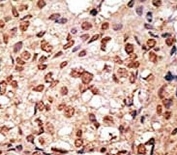

Titration of the SIGLEC7 antibody may be required due to differences in protocols and secondary/substrate sensitivity.

A portion of amino acids 1-30 from the human protein was used as the immunogen for this SIGLEC7 antibody.